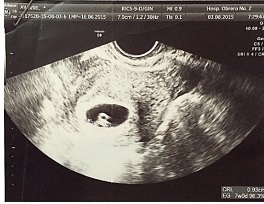

La evolución posoperatoria fue favorable, se realizó una ultrasonografía transvaginal que revelo embrion intrauterino con vitalidad ( Figura 3) La paciente fue dada de alta a los dos días de la intervención recibiendo progesterona natural micronizada 400 mg vía vaginal cada día.